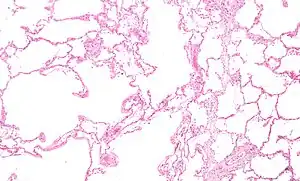

Micrograph showing emphysema (left – large empty spaces) and lung tissue with relative preservation of the alveoli (right)

Narrowing of the airways occurs due to inflammation and scarring within them. This contributes to the inability to breathe out fully. The greatest reduction in air flow occurs when breathing out, as the pressure in the chest is compressing the airways at this time.[73] This can result in more air from the previous breath remaining within the lungs when the next breath is started, resulting in an increase in the total volume of air in the lungs at any given time, a process called hyperinflation or air trapping.[73][74] Hyperinflation from exercise is linked to shortness of breath in COPD, as breathing in is less comfortable when the lungs are already partly filled.[75] Hyperinflation may also worsen during an exacerbation.[76]